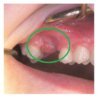

Гранульома або гранулема зуба – це вузлкове запалення м’

Гранульома або гранулема зуба –